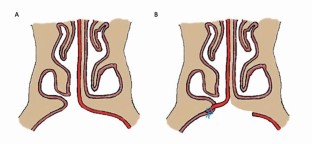

Primary cleft surgery refers to the planned surgical procedure(s) necessary to reconstruct an orofacial defect according to a specified protocol; in the context of a unilateral cleft lip and palate, this would include lip repair (with vomer flap closure of the hard palate), subsequent repair of the residual soft palate cleft and finally, the alveolar bone graft. This paper will provide an overview of the goals of primary surgical reconstruction, including the utility of pre-surgical orthopaedic techniques, including nasoalveolar moulding. The surgical methods of primary lip repair in both unilateral and bilateral clefts will be outlined and the concept of a primary rhinoplasty will be introduced. The principal techniques of cleft palate reconstruction will be delineated for a variety of cleft phenotypes. The final element of the primary reconstructive sequence is the alveolar bone graft using cancellous bone harvested from the iliac crest at approximately 8-10 years of age. The role of optimising oral hygiene prior to bone grafting cannot be over-emphasised and the utility of pre-surgical orthodontic arch expansion is also discussed. In the UK, bone graft outcomes are audited using the Kindelan score, which is evaluated from the six-month postoperative upper standard occlusal radiograph.

Hay N, Patel B, Haria P, Sommerlad B. Maxillary Growth in Cleft Lip and Palate Patients, With and Without Vomerine Flap Closure of the Hard Palate at the Time of Lip Repair: A Retrospective Analysis of Prospectively Collected Nonrandomized Data, With 10-Year Cephalometric Outcomes. Cleft Palate Craniofac J 2018; 55: 1205-1210.